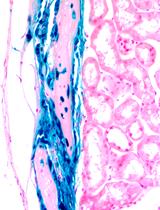

AxioVison 4.7. Z-stack images in the red (membrane tomato red), green (membrane EGFP) and blue (DAPI) channels were taken for each collection time point. Conversion of red to green was noted at each of the time points (Figure 3).

Figure 3. Engraftment and differentiation of the hair follicle bulge-derived stem cells into corneal epithelial cells. Single color images taken from a Z-stack depicting the cellular localization of membrane tomato red and membrane EGFP at 3 days and 5 weeks post-transplantation. Magnification x200. Reprinted with permission from Meyer-Blazejewska et al., 2011.